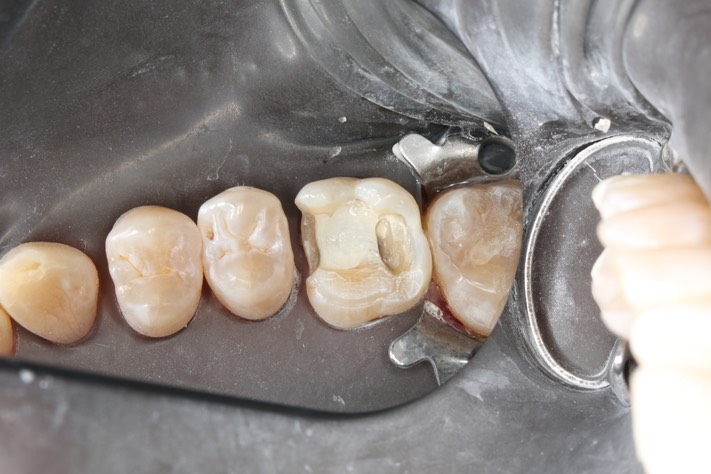

Matt Dodson #3 reprep

23Matt Dodson #3 reprep